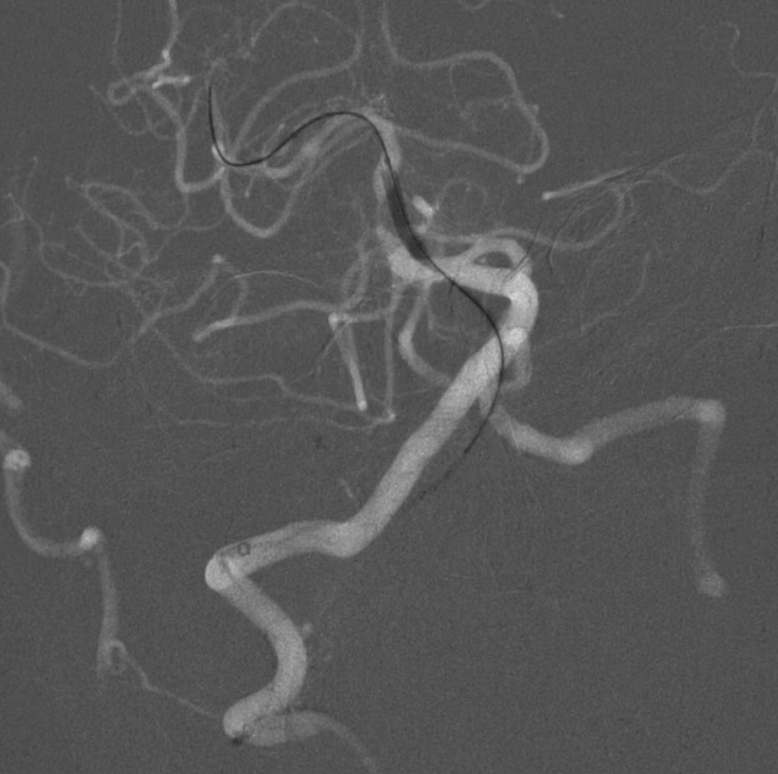

图4:输送性球囊微导管扩张基底动脉中段狭窄处。

图5:球囊扩张后行颅内自膨支架植入术,术后血管形态明显改善,残余狭窄20%。